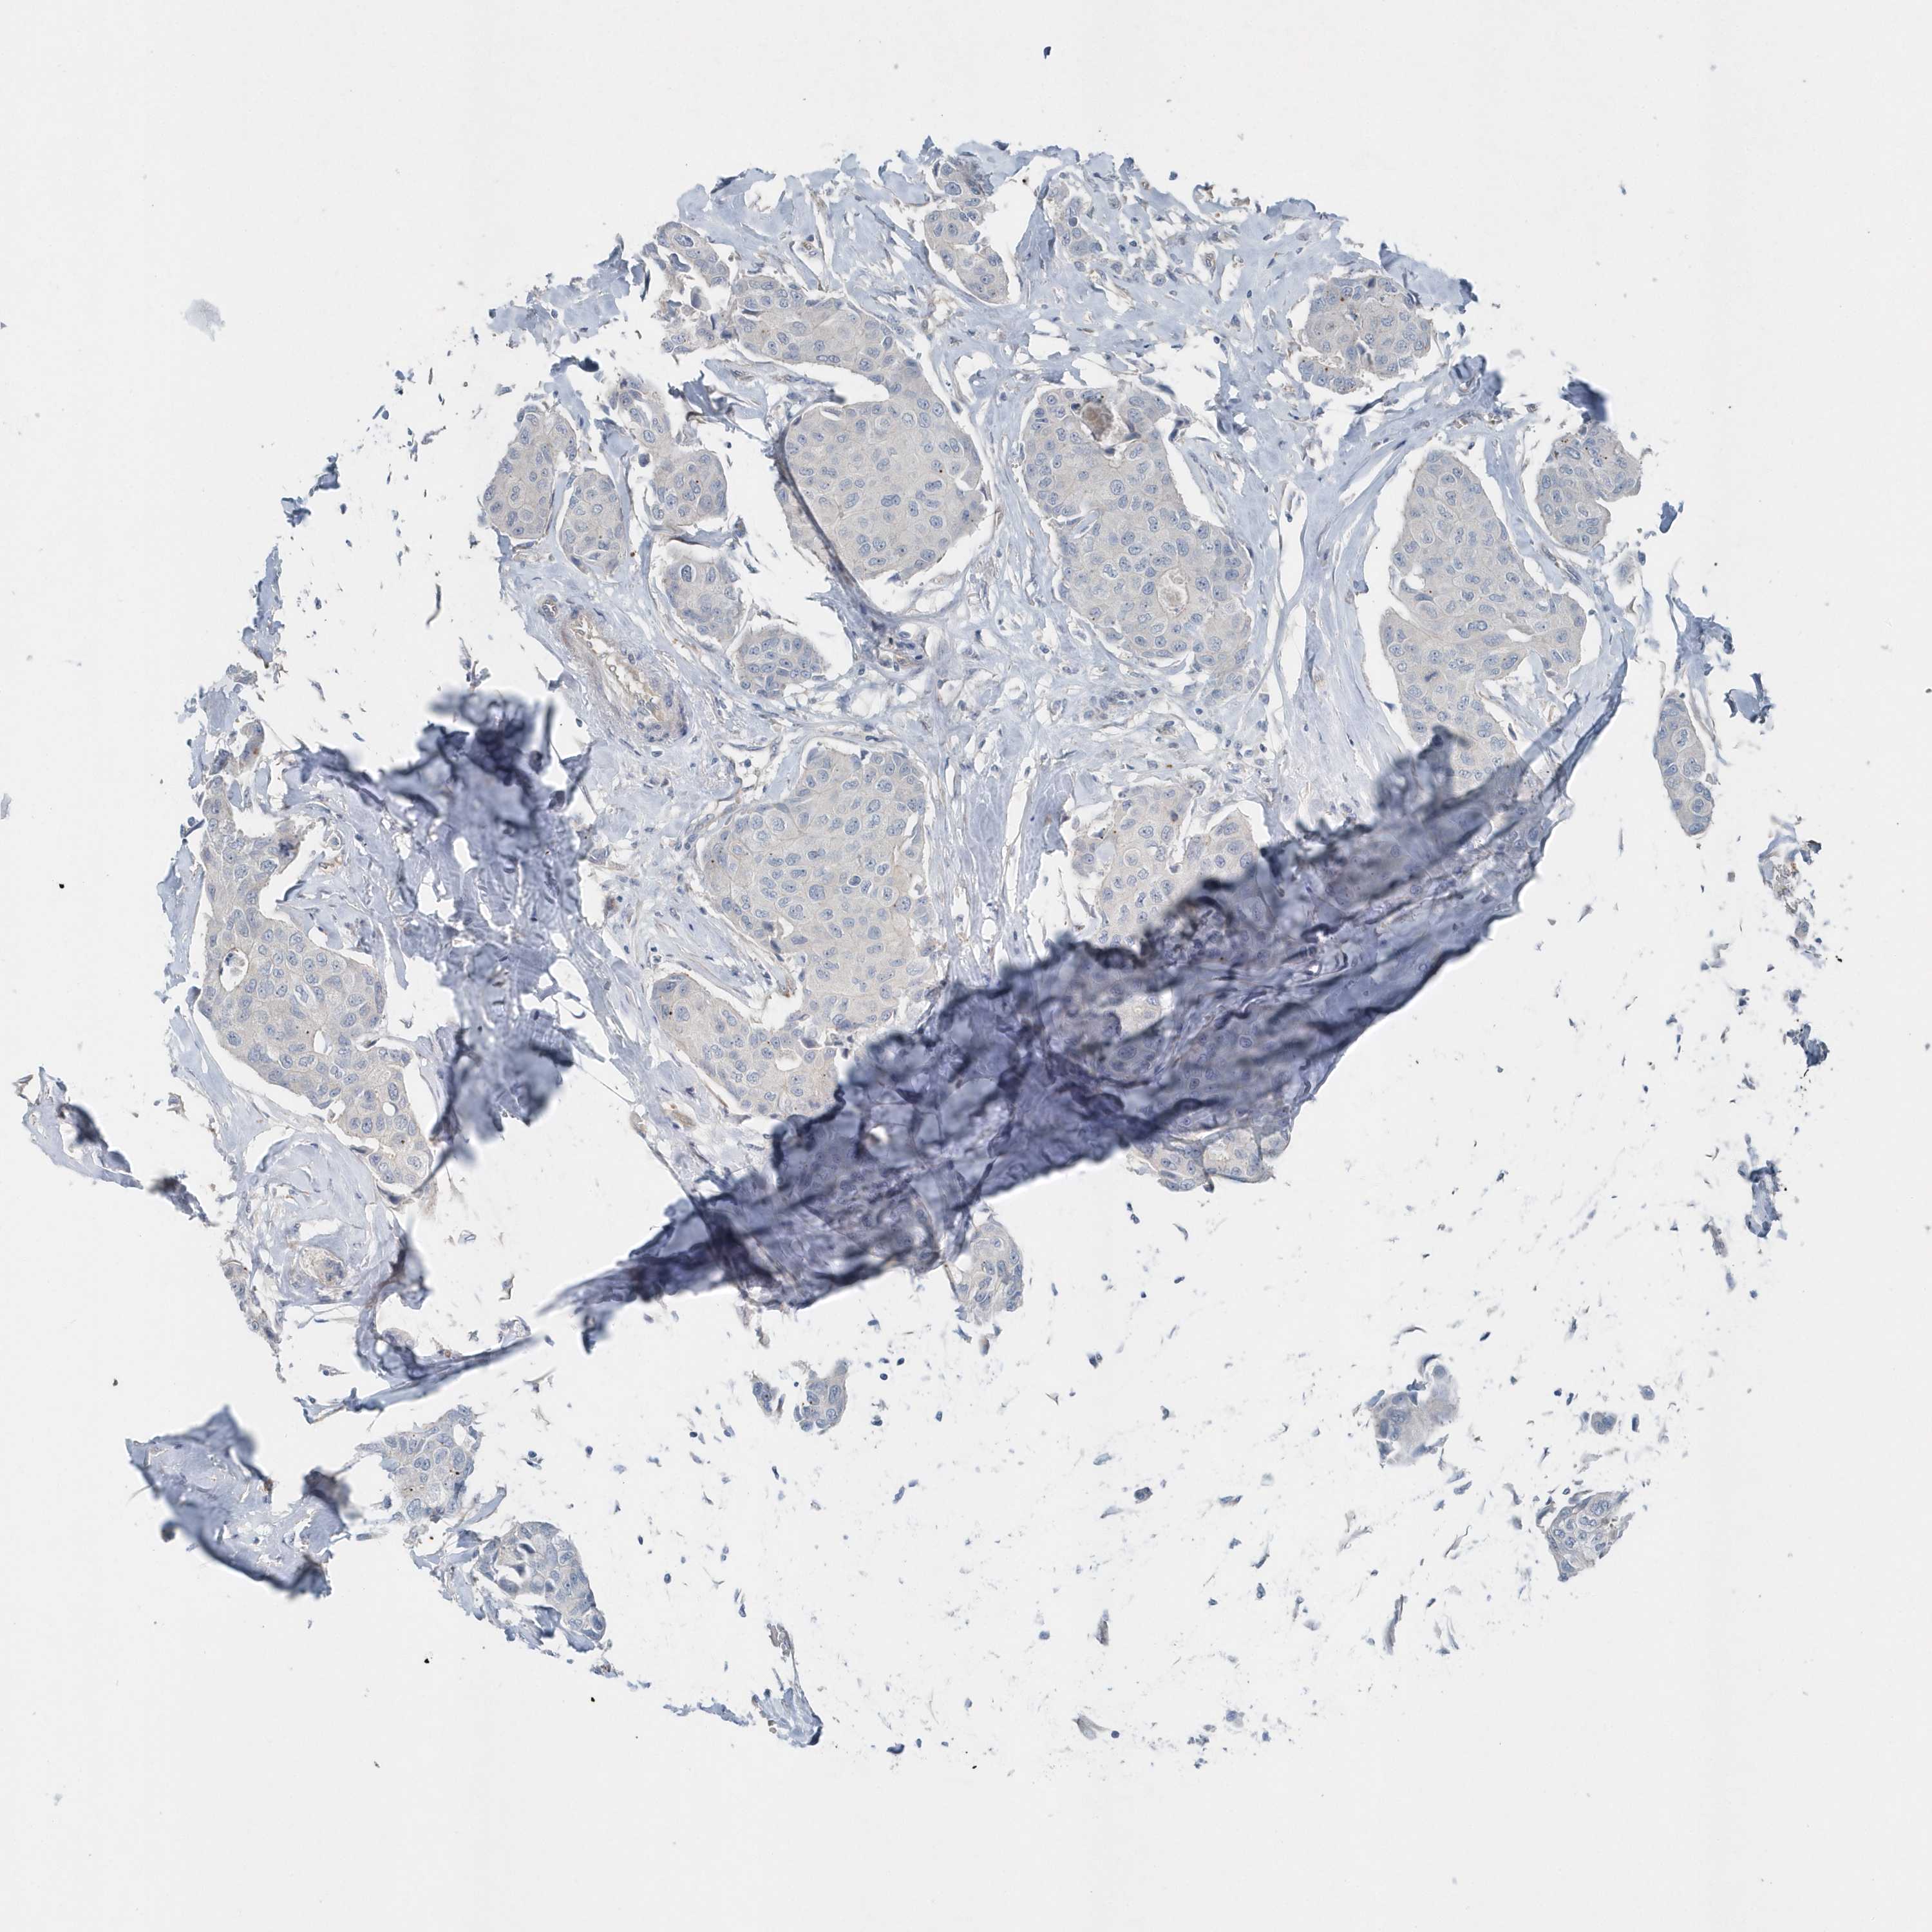

CANCER BREAST CANCER Show tissue menu

BRCA TCGA BRCA VALIDATION PROTEIN EXPRESSION